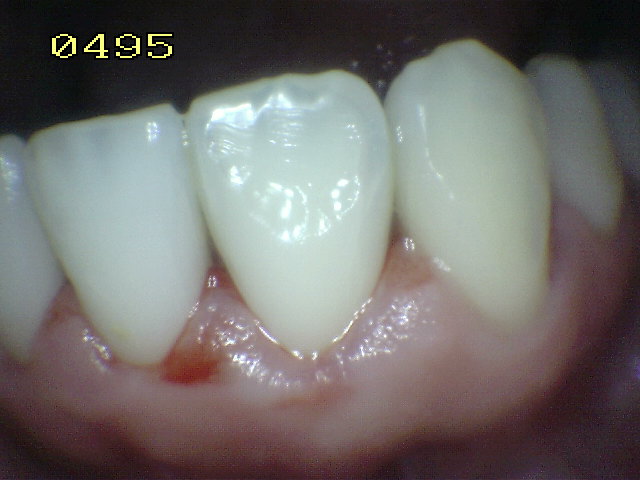

Casos clínicos de fluorosis leve.

Se caracteriza por esmalte normal, liso, traslucido y cristalino de color uniforme. Estas características  permanecen aún después del secado con aire prolongado